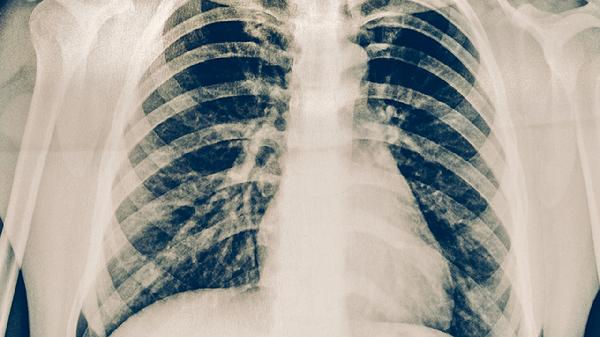

持续咳嗽咳痰超过2周、低热盗汗、痰中带血等症状需及时就诊。结核菌素试验、γ-干扰素释放试验、胸部CT等可辅助诊断。确诊患者应规范服用异烟肼片、利福平胶囊、吡嗪酰胺片等抗结核药物,完成全程治疗。

预防肺结核需建立健康生活方式,保证每日300-500克新鲜蔬菜水果摄入,适量补充维生素D和锌元素。每周进行3-5次有氧运动如快走、游泳等,每次持续30分钟以上。高危职业人群应每年进行胸部X线检查,接触结核患者后需医学观察至少8周。出现可疑症状时避免隐瞒病情,主动配合疾控部门开展流行病学调查和密切接触者筛查。